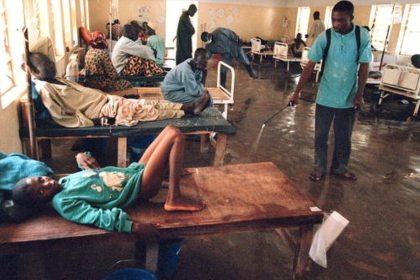

Nigeria : 27 décès et plus de 2.700 cas suspects de choléra signalés depuis début mai

Au moins 27 décès et 2.715 cas suspects de choléra ont été…